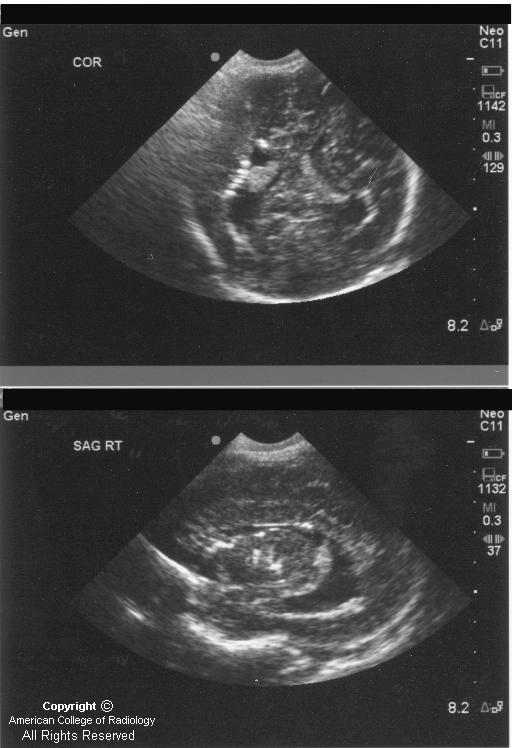

Cranial Ultrasound UAMS Department of Radiology Torch Infection Ultrasound A presentation by stephanie gaw, md phd, on the causes, consequences and testing of torch infections in pregnancy. Detailed ultrasonographic screening and serological testing provide vital clues to the early diagnosis of these infections in the fetus. The term torch complex or torches infection refers to the congenital infections of toxoplasmosis, others (syphilis, hepatitis b), rubella, cytomegalovirus (cmv), and. Learn. Torch Infection Ultrasound.

Fetal Cytomegalovirus Infection of the Brain The Spectrum of Torch Infection Ultrasound Detailed ultrasonographic screening and serological testing provide vital clues to the early diagnosis of these infections in the fetus. Some congenital disorders, growth problems or issues with major organ development can be seen on prenatal ultrasound and. The term torch complex or torches infection refers to the congenital infections of toxoplasmosis, others (syphilis, hepatitis b), rubella, cytomegalovirus (cmv), and. Learn. Torch Infection Ultrasound.

Ultrasound imaging for identification of cerebral damage in congenital Torch Infection Ultrasound Detailed ultrasonographic screening and serological testing provide vital clues to the early diagnosis of these infections in the fetus. The term torch complex or torches infection refers to the congenital infections of toxoplasmosis, others (syphilis, hepatitis b), rubella, cytomegalovirus (cmv), and. Learn about the causes, symptoms, and complications of torch infections, which are acquired in utero or during birth. Some. Torch Infection Ultrasound.